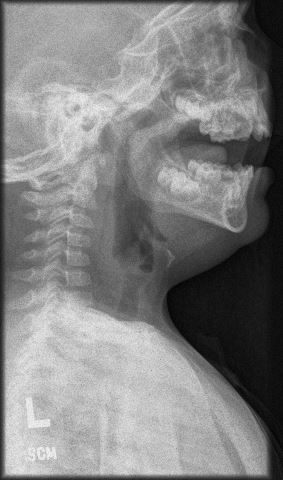

Diagnostic tests. The patient was sent for a stat soft-tissue neck radiograph, which showed air in the retropharyngeal space with thickened soft tissues, concerning for retropharyngeal abscess (Figure 1). He was sent to the emergency department, where a computed tomography scan was performed, the results of which showed a mucosal tear in the retropharyngeal soft tissues at the C2 level with associated retropharyngeal gas (Figures 2 and 3). He was admitted to the pediatric hospital for further evaluation and management.

Figure 1. Soft-tissue neck radiograph showing air in the retropharyngeal space.